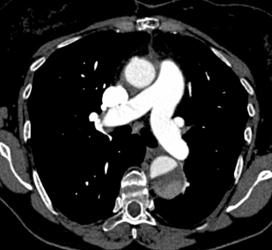

Diagnosis

Aortic Aneuryc With Editing Tool